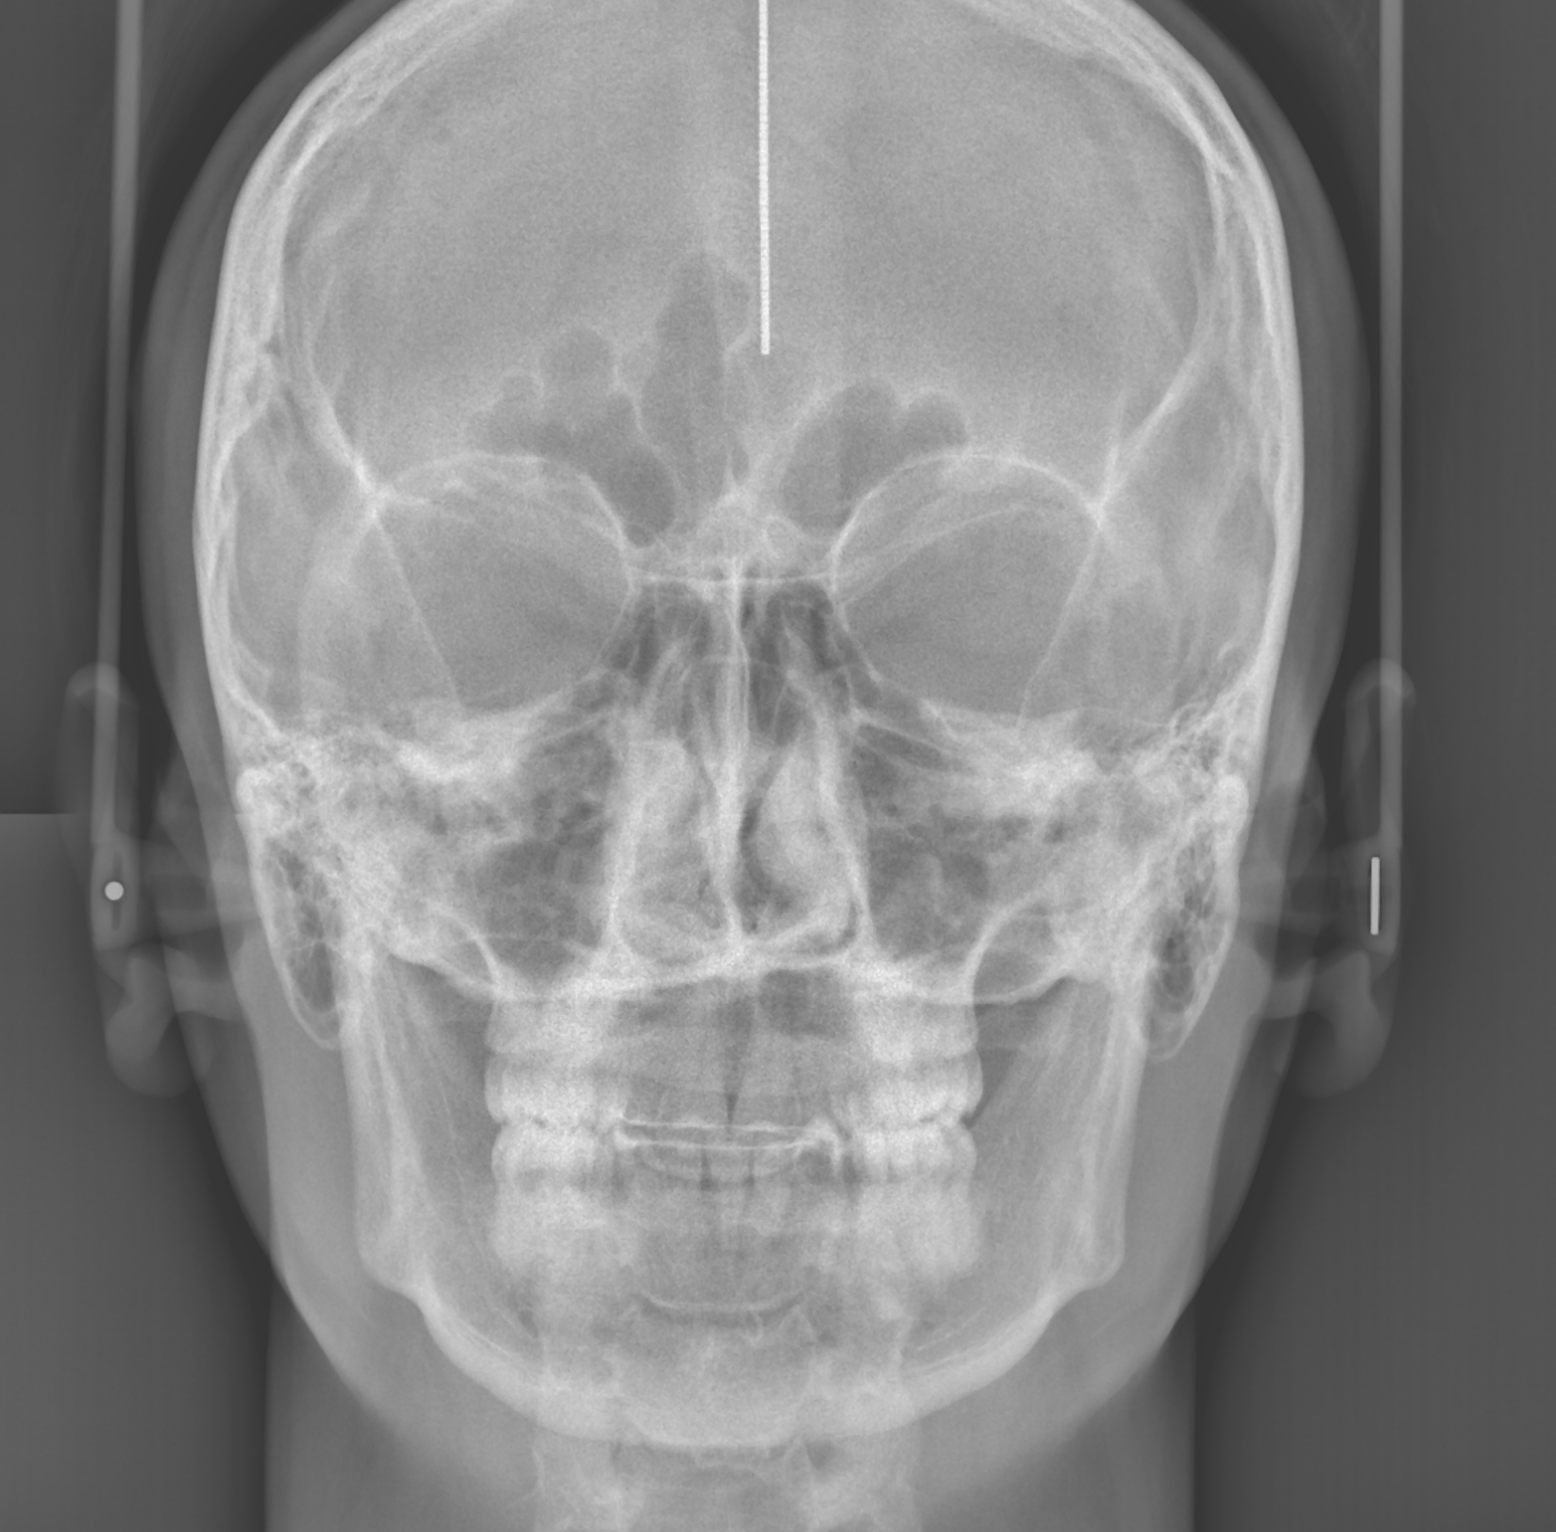

ТРГ прямої проекції

Телерентгенографія - це плоске двовимірне обстеження черепа в різних проекціях:

- Прямій

- Бічній

ТРГ є одним із найпопулярніших методів діагностики в ортодонтичній практиці, оскільки дозволяє оцінити скелетні співвідношення і провести необхідні вимірювання для корекції основних відхилень у структурі зубої̈щелепної системи: наприклад, розміру і положення щелеп, форми зубних дуг, розміру та прорізування зубів. Для більш точного аналізу в різних проекціях та виключення накладення тіней необхідна об'ємна комп'ютерна томографія, яка має максимальну інформативність.